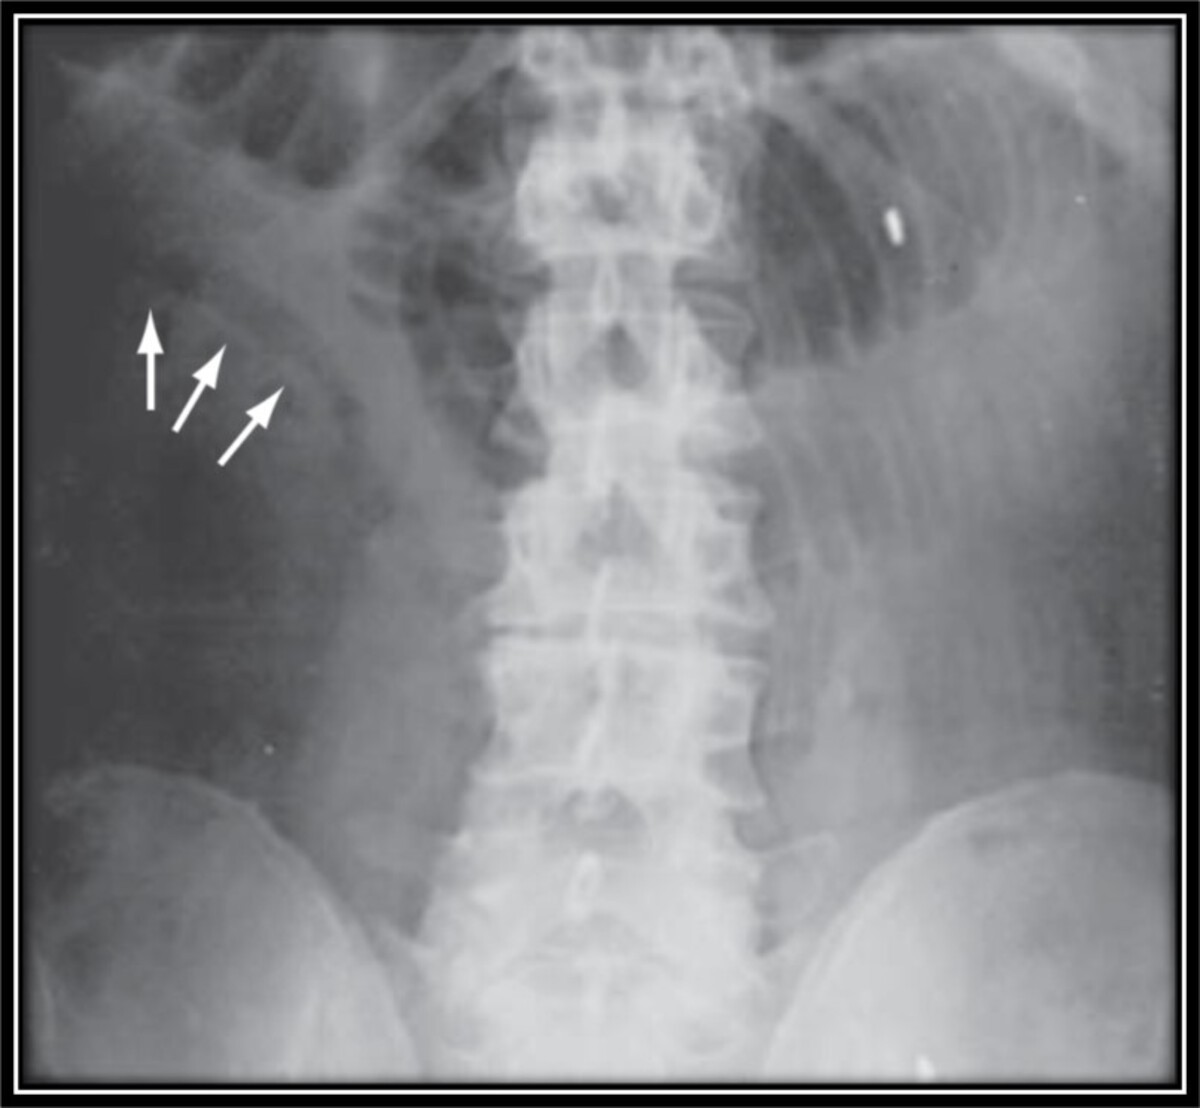

An abdominal x-ray is performed, and the results are shown in the figure. The ED calls and asks what you think the next most important step would be for this patient?

This patient is presenting with intermittent abdominal pains for several months in the setting of obesity and an oral contraceptive pill, both of which are risk factors for thrombotic processes. In addition, she reports that she has been to the ED intermittently and the week prior had an episode of enteritis. This is most consistent with a focal segmental ischemia that is evolving into an acute mesenteric ischemia from an atherosclerotic plaque in a branch of the superior mesenteric artery (SMA) that has now thrombosed. The modern classification for this is mesenteric arterial occlusive disease. The abdominal x-ray shows “thumbprinting” in the small bowel, a sign of mesenteric ischemia, along with dilations of the small bowel, consistent with development of an ileus. An ileus can also be seen in the setting of mesenteric ischemia. When a patient has a suspected mesenteric ischemia and if the ED has obtained a CT of the abdomen and pelvis, a call to the radiologist to review the images to ensure adequate visualization of the SMA is the most efficient next step to assess for patency and triage what should be done next. If the radiologist is unable to see the SMA and its branches, then consideration should be made for obtaining a CT angiogram. Of these next steps listed, a CT angiogram is the best option. A call to interventional radiology for angiography and presumably intervention is likely premature at this time as is obtaining a surgical consult, although surgery should be notified fairly rapidly when the diagnosis of acute mesenteric ischemia is obtained. A rapid colonoscopy would be the wrong step for this patient, and she would likely not survive the bowel preparation. An ultrasound with Doppler would not be helpful in this case.